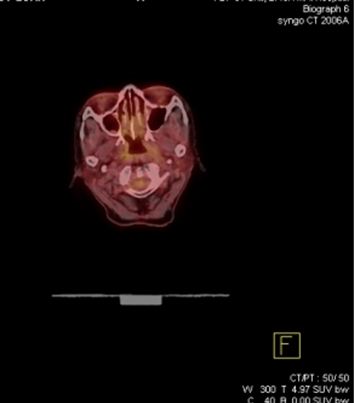

Mô phỏng tốt nhất trên PET/CT với hệ thống laser định vị 3 chiều. Vì PET/CT ghi hình dựa trên sự tập trung cao thuốc phóng xạ FDG vào các tế bào ung thư, cho hình ảnh chuyển hóa của khối u, sớm, chính xác hơn hình ảnh giải phẫu của CT đơn thuần (hình 1), xác định được mức độ xâm lấn của u cũng như phát hiện những di căn hạch kể cả với kích thước nhỏ ở mức độ phân tử, mức độ tế bào từ đó cho phép xác định thể tích xạ trị cũng như việc lập kế hoạch xạ trị được triệt để nhất (hình 2). Khi chụp mô phỏng: bệnh nhân trong tư thế nằm ngửa, cổ ưỡn sao cho đường thẳng giữa cằm - xương chũm vuông góc với mặt bàn; đầu bệnh nhân được giữ cố định bằng mặt nạ, tổng hợp từ loại chất dẻo đặc biệt.

Hình ảnh CT mô phỏng khó xác định được vị trí khối u

Hình ảnh PET/CT mô phỏng thấy rõ khối u vòm

Hình 1: Hình CT và PET/CT mô phỏng ung thư vòm.